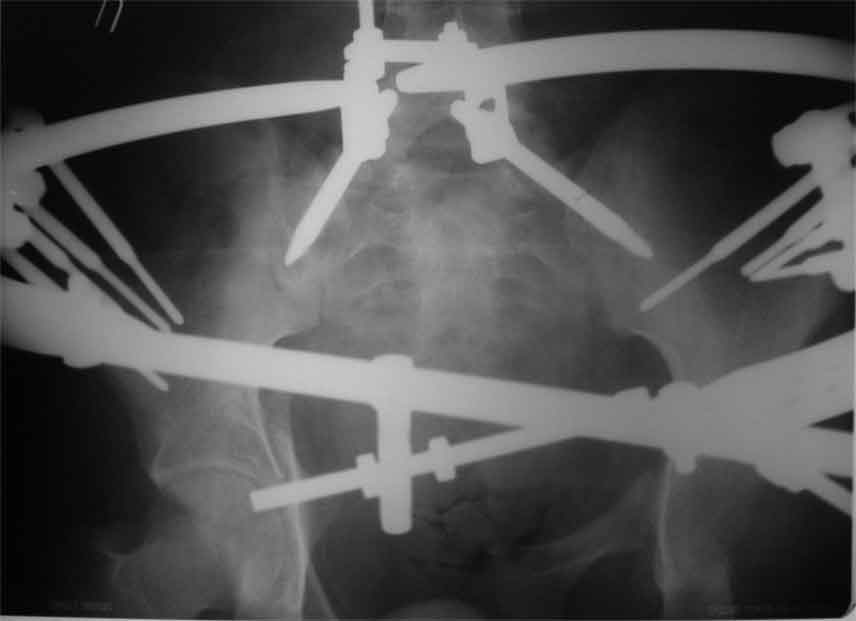

продолжение темы. не увидел энтузиазма в обсуждении. Вопросы прежние, первым этапом закрыто устранили вертикальное и передне-заднее смещение. Каким образом восстановить целостность тазового кольца, из каких доступов? Снимки в приложении